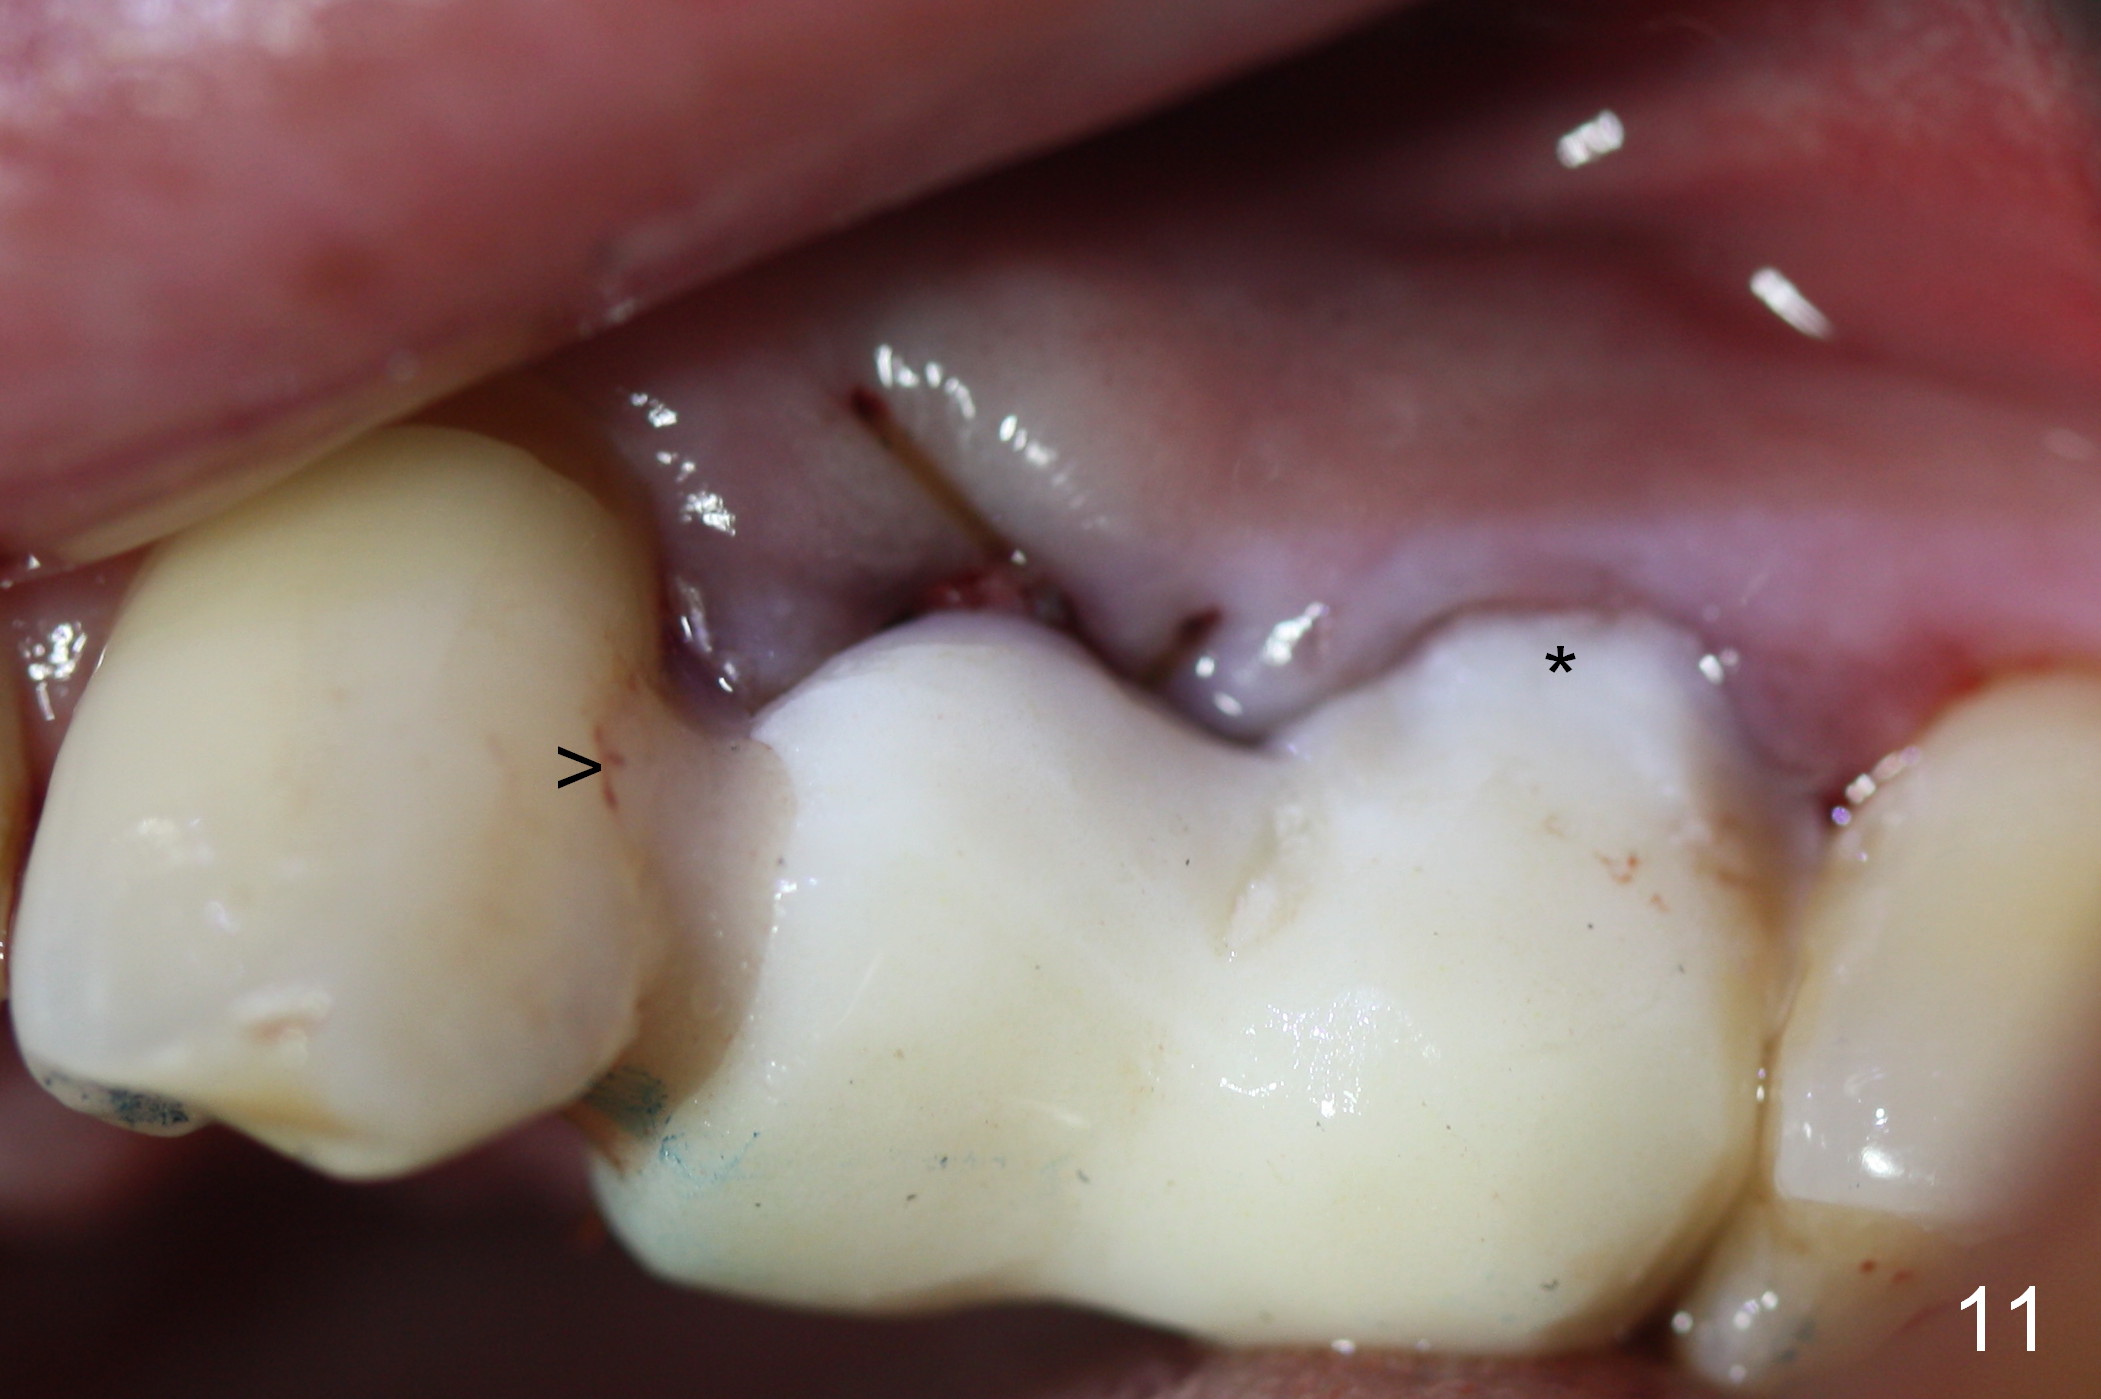

Taking 2 additional PAs with sensor 1 is frustrating (Fig.1,2), no apices shown.  Osteotomy is done smoothly with 2 mm pilot drill at 20 mm, 2.5 mm reamer at 17 mm, and 3 mm reamer at 14 mm and 4.5x20 mm tap at 17 mm.  The 1st intraop PA is taken with sensor 1 when 2 of 4.5x20 mm implants are placed (Fig.3); the implant at #12 is close to the root of the tooth #11.  The 2nd PA is taken with sensor 2: the apex of #11 touches the implant at #12 (Fig.4).  There is no separation when panoramic X-ray is taken (Fig.5).  Effort is exerted to re-direct the osteotomy twice (Fig.6: tap; Fig.7: implant) without success.  When the implant is removed, a PA is taken; it appears that the root of the tooth #11 has no damage (Fig.8).  To obtain the best recovery, socket preservation is carried out with 50/50 cortical/cancellous allograft mixed with Osteogen (Fig.12 *) and Collagen Dressing (Fig.9: #12).  A 2 (or 3)-unit provisional bridge (Fig.10: #12,13) is fabricated over the implant (Fig.9 I)/abutment (A) to cover these 2 sockets.  After acid etching #11 D surface (Fig.9 >) and relining (Fig.11 *), the provisional bridge is bonded to the tooth #11 (Fig.11,12 black >) so that bone graft will be less likely dislodged.